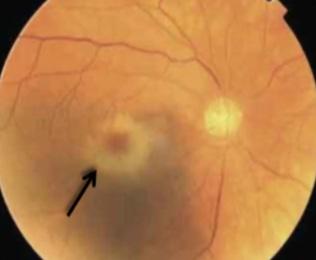

DIAGNÓSTICO

Fondo de ojo

♦ Lesiones atróficas amarillentas (toxoplasma)

♦ Lesiones necróticas hemorrágicas (citomegalovirus)

Figura 41. Coreorretinitis por toxoplasma: Lesiones atróficas amarillentas Figura 42. Coreorretinitis por citomegalovirus: Lesiones necróticas hemorrágicas Figura 40. Toxoplasmosis es la causa más frecuente de coreorretinitis